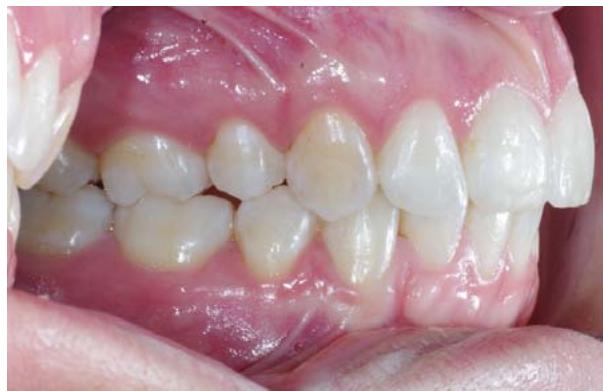

Vue du système de traction du côté droit, gauche, puis en vue occlusale.

Photos endobuccales de fin de traitement.